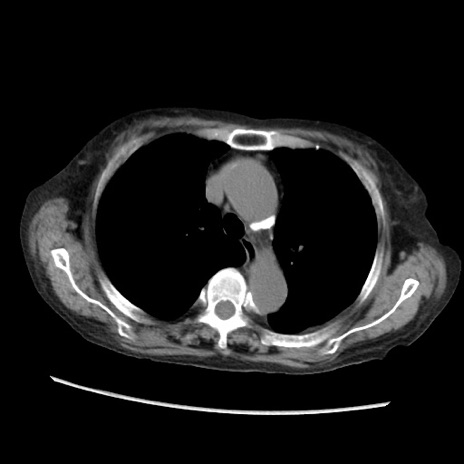

症例31(横断像)

【症例】80歳代 女性

【主訴】腹部膨満感

【現病歴】他院にて肝硬変にてフォロー中。1週間前から便秘、腹部膨満感、臍部腫瘤あり受診となる。

【既往歴】肝硬変

【身体所見】腹部膨隆あり、皮膚変化なし、疼痛なし。

【データ】WBC 4600、CRP 0.25